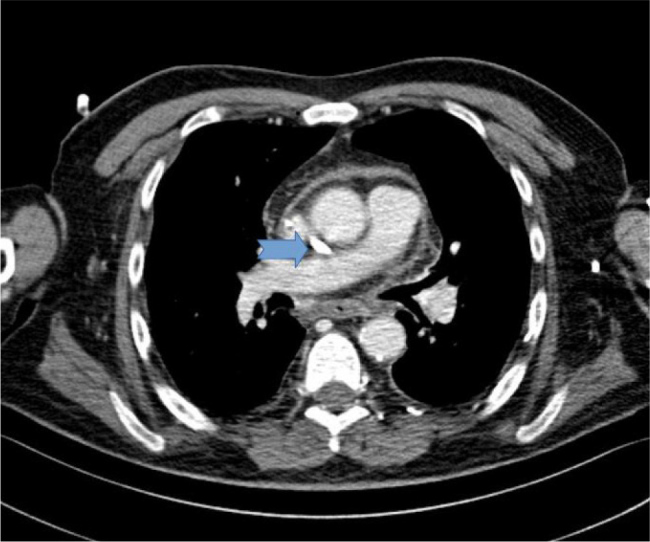

Case description: We report on a 68-year-old male on haemodialysis with SVC perforation and stenosis due to prolonged catheter use. After a failed guidewire-assisted exchange, a non-tunnelled CVC was successfully placed in the enlarged azygos vein under fluoroscopy. The patient continued haemodialysis without complications, and the two-month follow-up confirmed catheter patency.